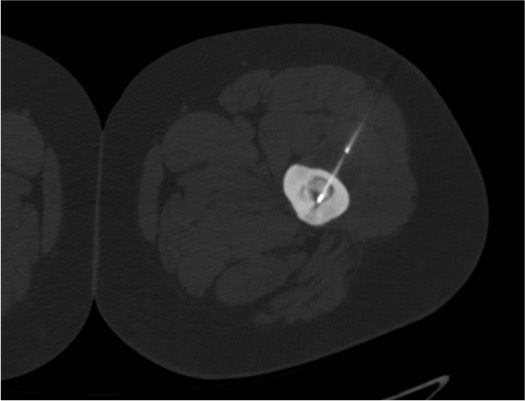

Advance bone access needle to nidus

Insert RFA probe

- Probe tip within 1 mm of nidus center — required for adequate ablation; minor displacement significantly reduces efficacy

- Active tip length must match nidus size: 1-cm tip for nidus ≤1 cm; 2-cm tip for larger nidus; overlap two 1-cm burns for nidus >1 cm if 2-cm probe unavailable

- Post-ablation CT: gas foci within the nidus confirm adequate heating; lack of gas may indicate incomplete ablation